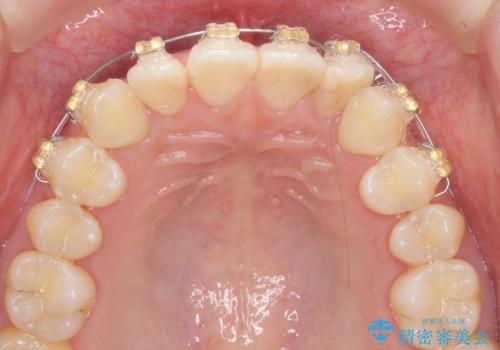

ワイヤー部分矯正治療を併用したマウスピース矯正治療

- 前歯のねじれ、深い噛み合わせ(ディープバイト)の改善を求めて来院されました。

マウスピースでは改善の難しい、歯のねじれ・ディープバイトを部分ワイヤー矯正で改善したのち、マウスピース矯正で全体の歯並びを整えていきます。

部分ワイヤー矯正を行ったことで前歯をしっかりと綺麗な歯並びへと導くことができました。